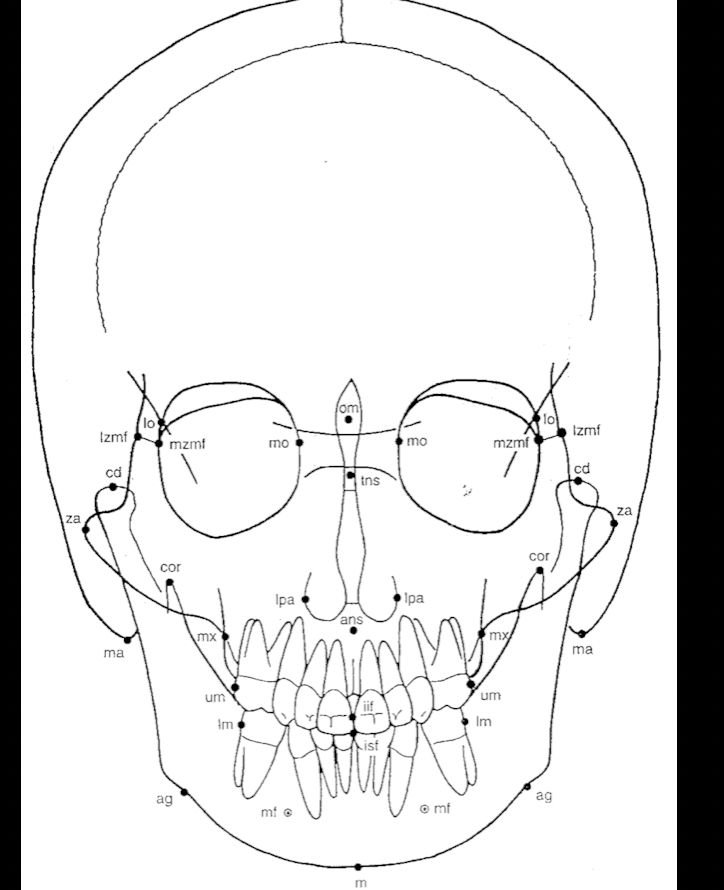

Q

What is this?

A

PA cephalometric